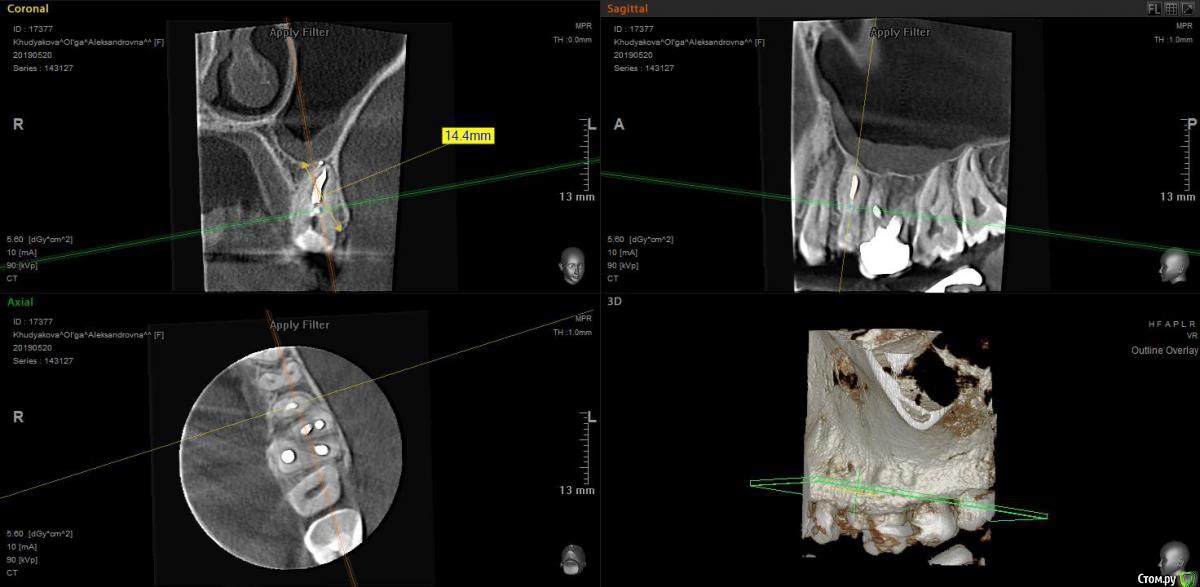

moises Опубликовано 21 мая, 2019 Поделиться Опубликовано 21 мая, 2019 (изменено) Добрый день,коллеги.Планируется удаление 25 зуба.Здесь целесообразно вести лунку под шайбой ,при условии что получится атравматично извлечь корень ?Или все таки альвостаз и направляющие швы?Планируется имплантация.P.S. на практике методику еще не применял) Изменено 21 мая, 2019 пользователем moises Ссылка на комментарий

колесников Опубликовано 21 мая, 2019 Поделиться Опубликовано 21 мая, 2019 Корень с таким бутылочным расширением редко удаётся удалить атравматично и целиком,обычно приходиться расщеплять и от него мало что остаётся. 2 Ссылка на комментарий